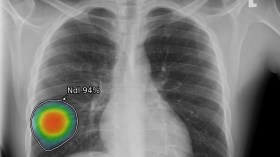

منظومة جديدة للذكاء الاصطناعي لرصد النتائج غير الطبيعية في الصور الشعاعية

الجزائر

2020/06/24